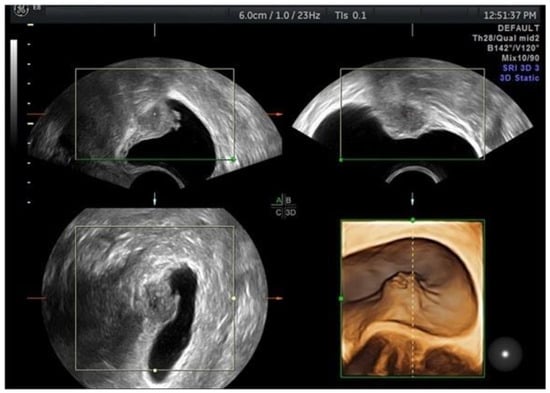

- Downey, D.B.; Fenster, A.; Williams, J.C. Clinical Utility of Three-dimensional US. RadioGraphics 2000, 20, 559–571. [Google Scholar] [CrossRef]

- Raine-Fenning, N.; Jayaprakasan, K.; Deb, S. Three-dimensional ultrasonographic characteristics of endometriomata. Ultrasound Obstet. Gynecol. 2008, 31, 718–724. [Google Scholar] [CrossRef]

- Guerriero, S.; Alcázar, J.L.; Ajossa, S.; Pilloni, M.; Melis, G.B. Three-Dimensional Sonographic Characteristics of Deep Endometriosis. J. Ultrasound Med. 2009, 28, 1061–1066. [Google Scholar] [CrossRef]

- Barra, F.; Alessandri, F.; Scala, C.; Ferrero, S. Ultrasonographic 3D Evaluation in the Diagnosis of Bladder Endometriosis: A Pro-spective Comparative Diagnostic Accuracy Study. Gynecol. Obstet. Investig. 2021, 86, 299–306. [Google Scholar] [CrossRef]

- Guerriero, S.; Saba, L.; Ajossa, S.; Peddes, C.; Angiolucci, M.; Perniciano, M.; Melis, G.B.; Alcázar, J.L. Three-dimensional ultrasonography in the diagnosis of deep endometriosis. Hum. Reprod. 2014, 29, 1189–1198. [Google Scholar] [CrossRef]

- Pascual, M.A.; Guerriero, S.; Hereter, L.; Barri-Soldevila, P.; Ajossa, S.; Graupera, B.; Rodriguez, I. Diagnosis of endometriosis of the rectovaginal septum using introital three-dimensional ultrasonography. Fertil. Steril. 2010, 94, 2761–2765. [Google Scholar] [CrossRef] [PubMed]